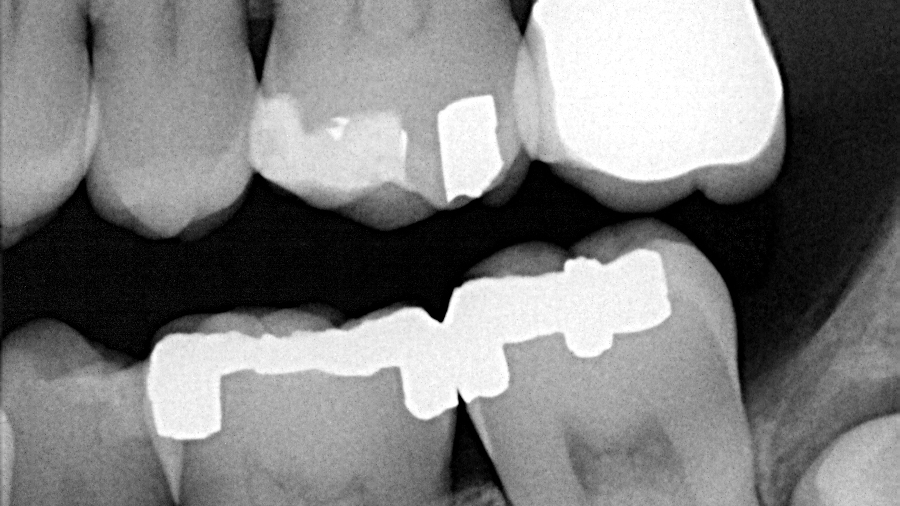

A healthy, 38-year-old male presented to the office for a comprehensive exam. His blood pressure was within normal limits, and no medications were being taken. Bitewing radiographs were taken, and it was noted that there was a cystlike lesion on what appeared to be a mesial impaction of no. 17. A panoramic radiograph indeed revealed a large, radiolucent/cystlike lesion surrounding a mesial/inferior-positioned no. 17. The widest point of the cyst measured approximately 3 cm. The patient reported knowing about the lesion but was not inclined to have it removed because it was not bothering him. The area was not tender to palpation; tooth no. 18 had normal pocketing and tested normal to cold, percussion, and bite.